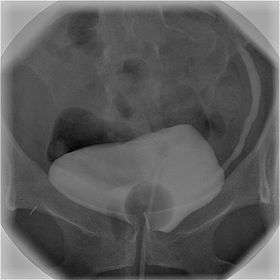

![]() Cystography image showing contrast in the urinary bladder and left ureter (right side of image). | |

Cystourethrography is a radiographic, fluoroscopic medical procedure that is used to visualize and evaluate the female urethra. Voiding and positive pressure cystourethrograms help to assess lower urinary tract trauma, reflux, suspected fistulas, and to diagnose urinary retention. Magnetic imaging (MRI) has been replacing this diagnostic tool due to its increased sensitivity.[1] This imaging technique is used to diagnose hydronephrosis, voiding anomalies, and urinary tract infections in children. abnormalities.[2]

Cysourethrography includes the voiding cystourethrogram (VCUG) and positive pressure urethrogram (PPUG).